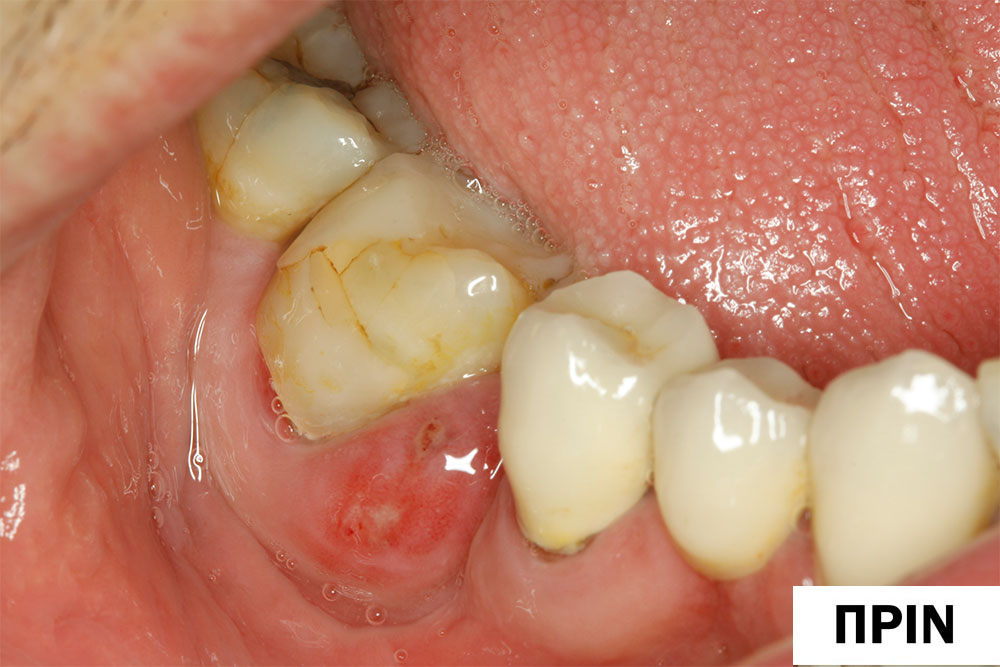

Θεραπεία περιοδοντικού αποστήματος με Laser